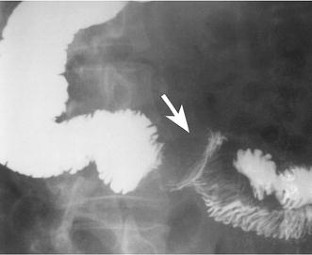

Fig. 1

Fig. 2

Fig. 3

Fig. 4

Fig. 5

Fig. 6

Fig. 7

Fig. 8